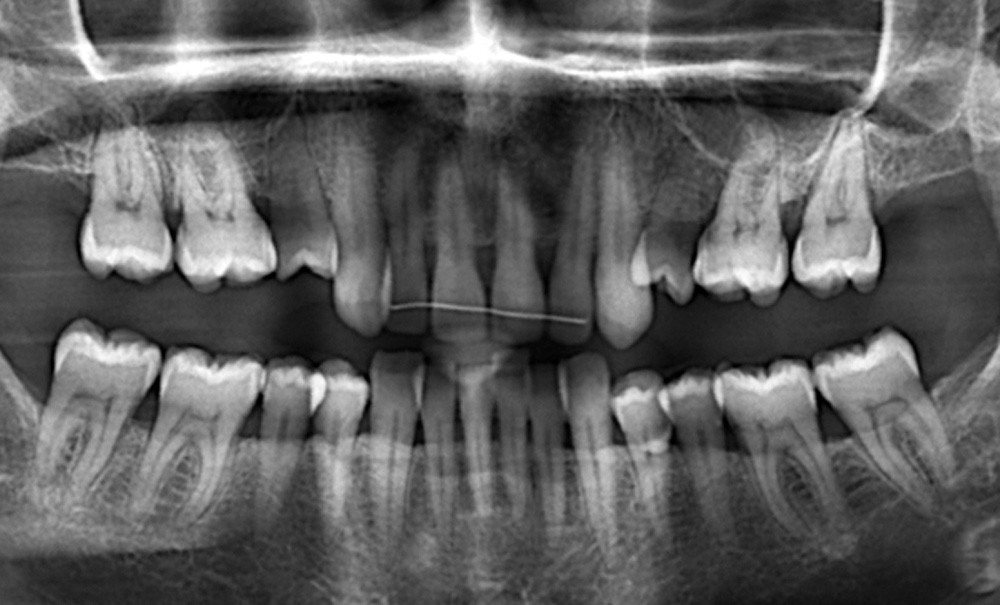

L’examen clinique révèle une maladie parodontale chronique, et la patiente est orientée immédiatement chez notre correspondant parodontiste.

Madame P. effectue l’ensemble du traitement parodontal et ne revient que trois ans plus tard (ce délai entre la première consultation et la décision de traitement est très commun chez le patient adulte, et ne constitue nullement un mauvais pronostic pour le futur traitement orthodontique). Nous pouvons maintenant travailler à partir de l’examen clinique et sur les documents radiologiques et photographiques de 2016.